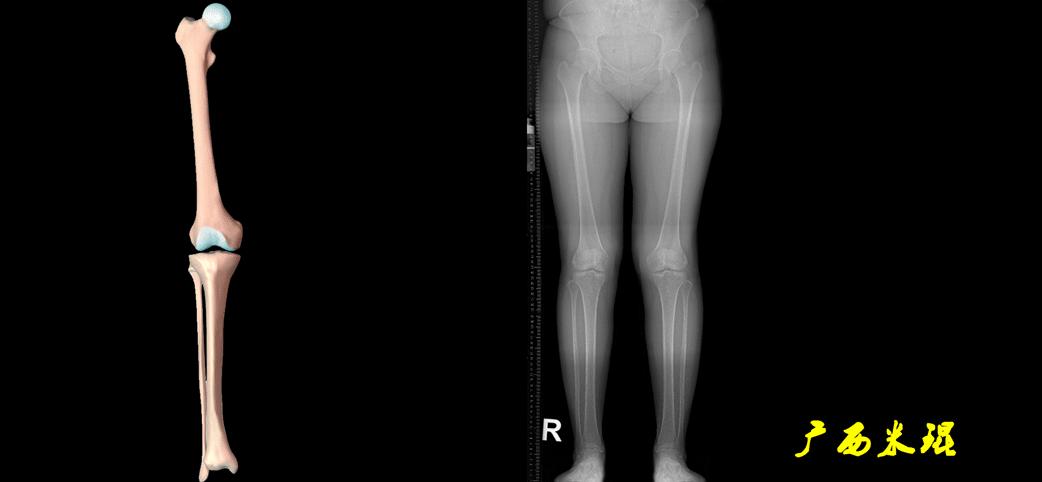

下肢力线及相关角度测量的前提是必须拍摄标准的站立位也就是负重位的下肢全长片。目前这样的照片都是放射科的技师在电脑上拼接出来的,大部分医院的DR都能够做到这一点。

患者直立于摄影架上,后背贴近摄影架,双手自然下垂,膝关节尽量伸直,足部与双肩同宽,要求投照时双髌骨朝正前方,通常患者双足尖应平行向前即可。

提醒一下大家,拍摄过程中应避免下肢的外旋和内旋。如果有一侧肢体短缩时,投照应当用脚垫垫高短缩肢体,使骨盆保持水平,这样下肢短缩测量才精确。如果有肢体旋转畸形时,还是以髌骨朝前为标准,虽然此时双足可能不能保持平行。

无论如何,拍摄出来的下肢全长片必须包含髋关节中心、膝关节中心及踝关节中心,否则对临床是无用的。有了一张下肢的全长照片,我们需要确定下肢关节的中心点,通过中心点画出下肢的各种轴线,然后利用轴线与关节线的相交得出各种所需要的角度。

机械轴要分前后位及侧位,站立前后位(也就是冠状面)股骨头中心与踝关节中心的连线通过膝关节中心,这是下肢的机械轴线,也就是下肢力线,常说Mikulicz线。冠状面的力线评估在临床工作中最常用、最基础、最重要。

最常见的下肢畸形发生于冠状面,即膝内外翻畸形,冠状面的对线异常通过应用“对线异常检验”进行分析,机械轴的偏移(MAD)表现为对线异常。

膝内翻是指下肢力线通过膝关节中心点内侧,距中点2mm以上,偏内超过15mm为显著膝内翻。膝外翻是指下肢力线通过膝关节中心点外侧,距中点2mm以上,偏外超过10mm为显著膝外翻。